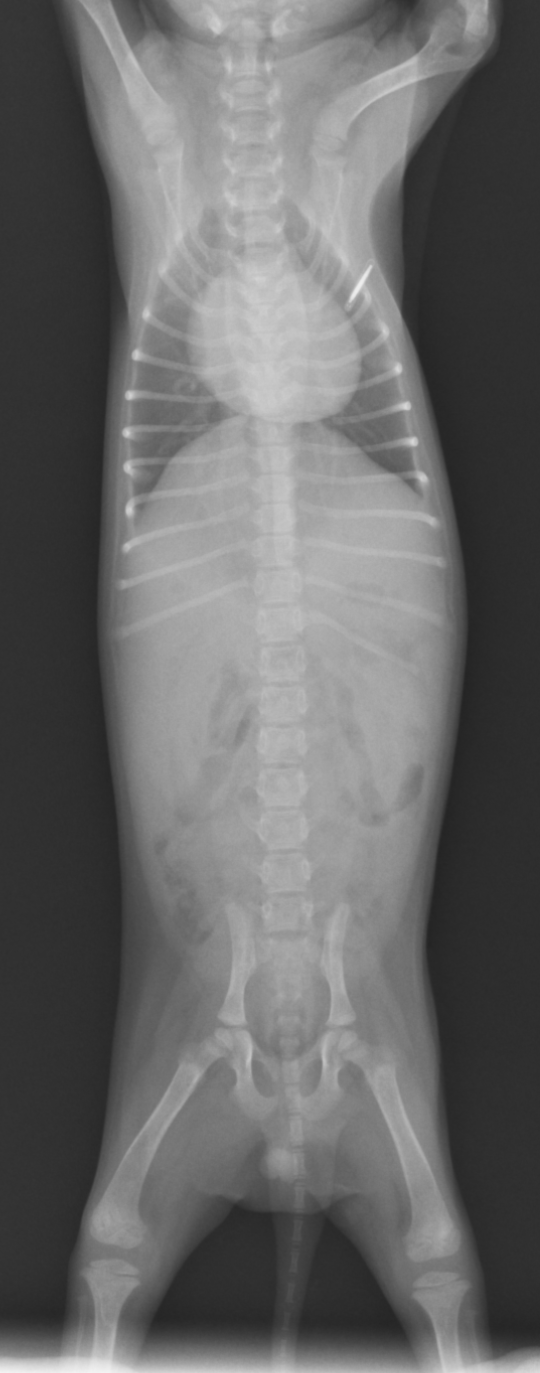

今回ご紹介するのは1週間前に軟便から始まり持続的な下痢を主訴に来院された症例をご紹介します。症例は、2ヶ月齢のポメラニアン、未避妊雌で来院前日から食欲が落ち元気がないということでした。当院ではまず血液検査、X線検査、糞便検査を行いました。

X線検査では、特に大きな異常はありませんでした。